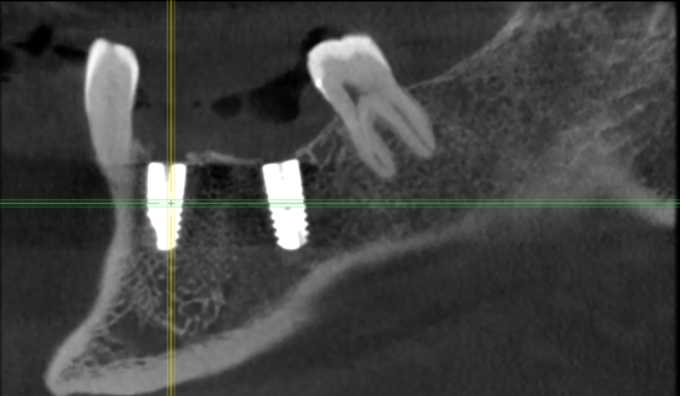

m-art-a23 Опубликовано 21 апреля, 2021 Поделиться Опубликовано 21 апреля, 2021 Здравствуйте. Два дня назад мужу установили 5 имплантов Ankylos на нижнюю челюсть (2+3). Спустя 30-40 мин после операции появилась сильная острая боль, которая не уменьшается по настоящее время. Боль похожа по ощущениям на пульпитную, не снимается никакими НПВС, кроме кеторолака. А/б, А/гистаминные, холод местно, хлоргексидин - все рекомендации выполнялись. На осмотре врачом не обнаружено следов воспаления, КТ сделал - без особенностей. Что может служить причиной такой боли, сколько она может длиться и что делать в данной ситуации? Врач-имплантолог ничего внятного не предложил. Ссылка на КТhttps://cloud.mail.ru/public/EvKn/ULqxLy6BD Ссылка на комментарий

m-art-a23 Опубликовано 22 апреля, 2021 Автор Поделиться Опубликовано 22 апреля, 2021 Да, снимок видел, сказал, что до нерва километр и что все поставлено хорошо. Болит вся челюсть. И справа и слева, но слева сильнее. Там, где три импланта, боли сильнее. Онемения нет Ссылка на комментарий

red_butler Опубликовано 22 апреля, 2021 Поделиться Опубликовано 22 апреля, 2021 7 минут назад, m-art-a23 сказал: Нет, не один. Но он лучший. Скажите пожалуйста, что служит причиной боли, по-Вашему? Неужели все импланты нужно убирать только по Кт трудно судить, но есть вопросы по позиционированию имплантов... боль может быть вызвана перегревом кости во время формирования ложа импланта, но в этом случае она появляется примерно с третьего дня. Так же боль может вызывать гиперкомпрессия импланта, и может болеть кость если ее придавили формирователем десны. Я бы обсудил с хирургом удаление среднего импланта слева 1 Ссылка на комментарий

Irouil Опубликовано 22 апреля, 2021 Поделиться Опубликовано 22 апреля, 2021 Я бы рекомендовал удаление среднего импланта слева, независимо от наличия/отсутствия болевых ощущений боль может быть признаком каких-то описанных моим коллегой процессов, а может ничего кроме самой боли не означать (менее вероятно, но и такое бывает). Если удаление упомянутого импланта поможет против болевого синдрома - это win-win если хирург не видит необходимости удаления импланта, я бы рекомендовал сходить на осмотр к ортопеду, который будет в будущем эти импланты протезировать. Возможно у него найдутся весомые аргументы для коллеги 3 Ссылка на комментарий

Irouil Опубликовано 22 апреля, 2021 Поделиться Опубликовано 22 апреля, 2021 (изменено) 1 час назад, m-art-a23 сказал: Благогдарю за совет. Если Вам не трудно, объясните пожалуйста, что не так со средним имплантом. Описанные процессы, если таковые имеют место быть, должны постепенно прийти в норму? Другими словами, сколько еще нужно времени, чтобы окончательно принять решение об удалении импланта (имплантов)? Сегодня третьи сутки после установки. Боль сохраняется. Средний имплант расположен чрезвычайно близко к соседнему, расположенному кпереди от него. С очень большой долей вероятности это может привести к значительной резорбции (убыли) костной ткани между ними, что для любых имплантов очень вредно, а для конкретно Анкилосов - губительно из-за особенностей их протезирования. Если неблаготворные процессы (компрессионный или термический некроз) присутствуют, то импланты просто не интегрируются (не приживутся) - те, что зашиты не выдержат нагрузки при раскрытии, а тот, на котором стоит ФДМ - расшатается через 2-3 недели. Это не призыв проверять его стабильность языком, сейчас его лишний раз лучше не трогать. В норме после имплантации боли держатся 1-2 дня, если все не очень хорошо - держатся 2-3 недели, но даже в таком случае имплант может интегрироваться, поэтому решение об его удалении в таком случае должно, по моему убеждению, быть совместным между врачом и пациентом, и приниматься в индивидуальном порядке Изменено 22 апреля, 2021 пользователем Irouil Ссылка на комментарий